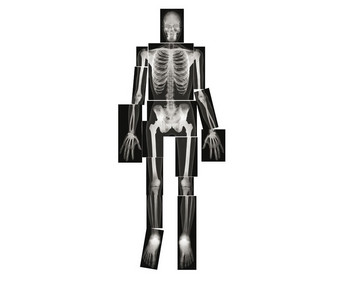

Röntgenbilder Mensch

lebensgroße Aufnahmen

- insgesamt 1,5 m groß

- 18 Detailaufnahmen

- für ein komplettes Gesamtbild

Ein vollständiges Skelett entdecken

Halten Sie diese lebensgroßen Röntgenaufnahmen einer jungen erwachsenen Person gegen das Licht (z. B. die Fensterscheibe). Auch auf einem Lichttisch lassen sich die Aufnahmen gut anschauen. Auf diesen Röntgenaufnahmen können Ihre Schülerinnen und Schüler einen echten Skelettaufbau betrachten. Nach genauer Sichtung der 18 verschiedenen Detailaufnahmen können die Teile zu einem ganzen Skelett zusammengelegt werden.

Aufnahmen:

- Brustkorb 35 x 28,5 cm

- Arme: 45 x 11,5 cm

- Beine 36,5 x 15 cm

- Becken: 31 x 22,5 cm